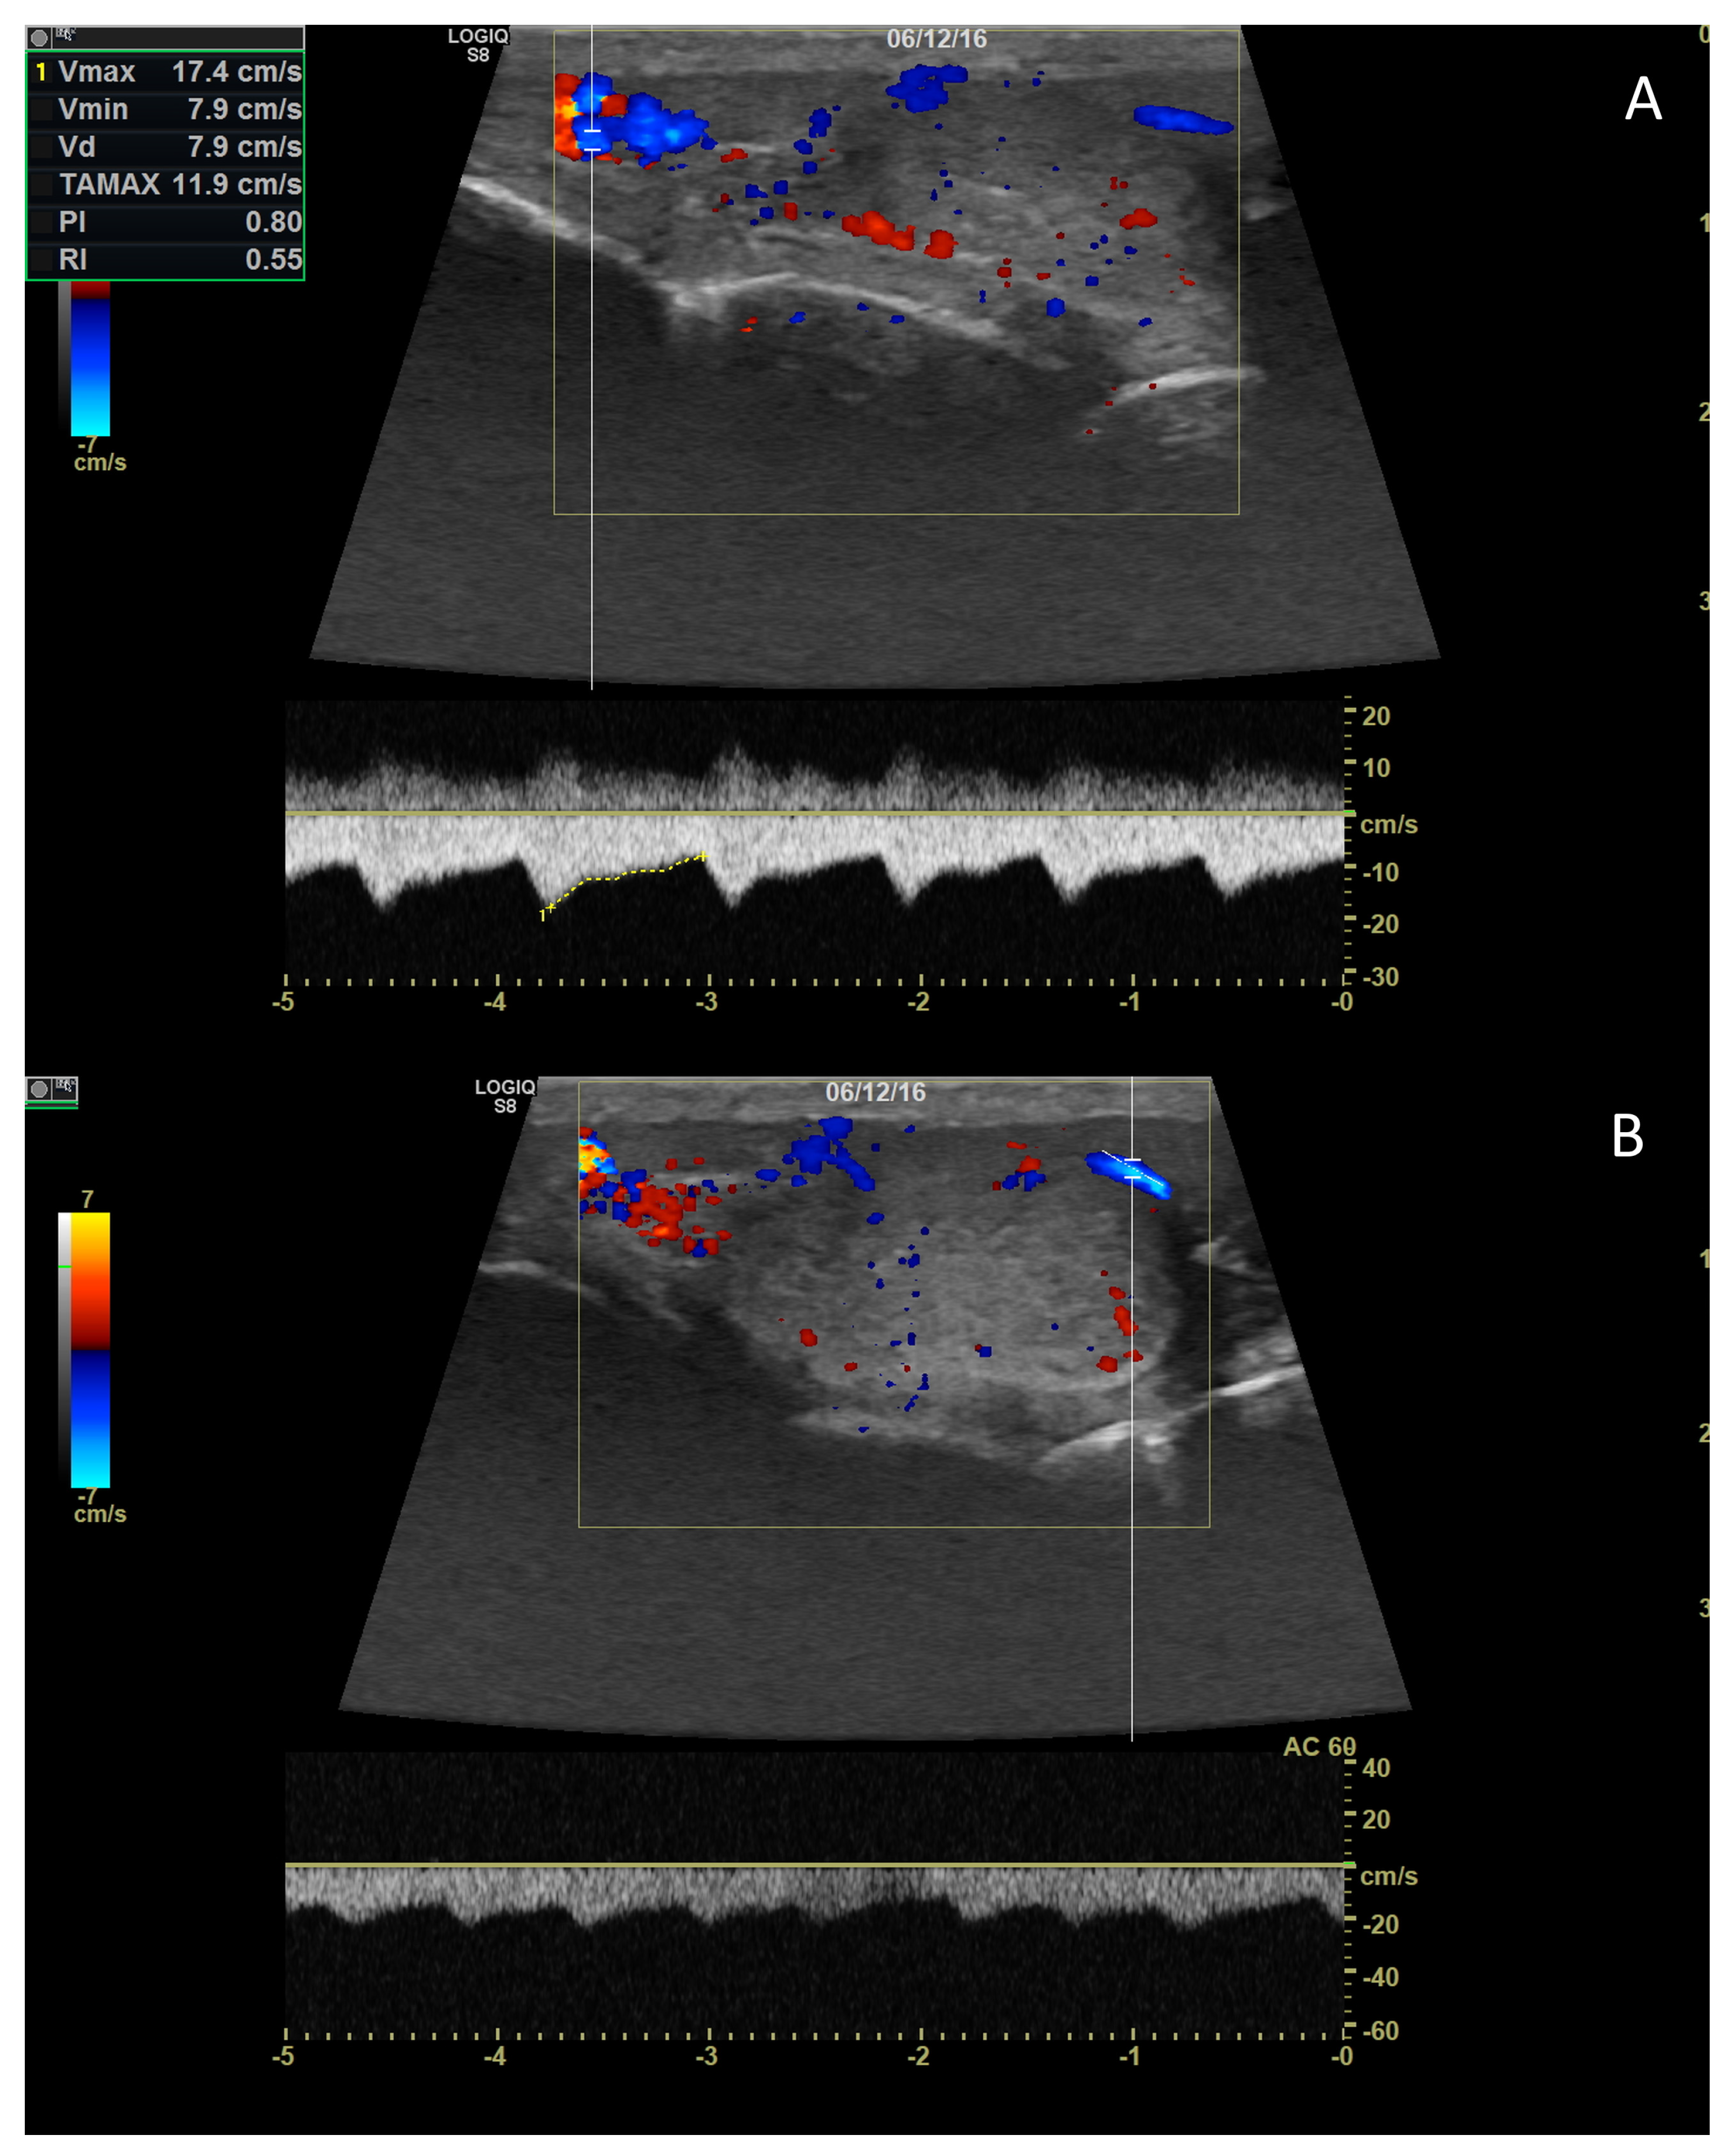

4. Colour Doppler and Power Doppler

4.1. Technology and Applications

4.2. Normal Findings

4.3. Relationship between Spectral Doppler Measurement and Dog’s Semen Quality

4.4. Abnormal Findings

- Bigliardi, E.; Denti, L.; De Cesaris, V.; Bertocchi, M.; Di Ianni, F.; Parmigiani, E.; Bresciani, C.; Cantoni, A.M. Colour Doppler Ultrasound Imaging of Blood Flows Variations in Neoplastic and Non-Neoplastic Testicular Lesions in Dogs. Reprod. Dom. Anim. 2019, 54, 63–71. [Google Scholar] [CrossRef]

- Carrillo, J.; Soler, M.; Lucas, X.; Agut, A. Colour and Pulsed Doppler Ultrasonographic Study of the Canine Testis: Doppler Ultrasound Testis Dog. Reprod. Domest. Anim. 2012, 47, 655–659. [Google Scholar] [CrossRef]

- De Souza, M.B.; Barbosa, C.C.; England, G.; Mota Filho, A.C.; Sousa, C.; de Carvalho, G.G.; Silva, H.; Pinto, J.N.; Linhares, J.; Silva, L. Regional Differences of Testicular Artery Blood Flow in Post Pubertal and Pre-Pubertal Dogs. BMC Vet. Res. 2015, 11, 47. [Google Scholar] [CrossRef]

- De Souza, M.B.; England, G.C.W.; Mota Filho, A.C.; Ackermann, C.L.; Sousa, C.V.S.; de Carvalho, G.G.; Silva, H.V.R.; Pinto, J.N.; Linhares, J.C.S.; Oba, E.; et al. Semen Quality, Testicular B-Mode and Doppler Ultrasound, and Serum Testosterone Concentrations in Dogs with Established Infertility. Theriogenology 2015, 84, 805–810. [Google Scholar] [CrossRef]

- De Souza, M.B.; da Cunha Barbosa, C.; Pereira, B.S.; Monteiro, C.L.B.; Pinto, J.N.; Linhares, J.C.S.; da Silva, L.D.M. Doppler Velocimetric Parameters of the Testicular Artery in Healthy Dogs. Res. Vet. Sci. 2014, 96, 533–536. [Google Scholar] [CrossRef] [PubMed]

- Gloria, A.; Di Francesco, L.; Marruchella, G.; Robbe, D.; Contri, A. Pulse-Wave Doppler Pulsatility and Resistive Indexes of the Testicular Artery Increase in Canine Testis with Abnormal Spermatogenesis. Theriogenology 2020, 158, 454–460. [Google Scholar] [CrossRef] [PubMed]

- Gumbsch, P.; Holzmann, A.; Gabler, C. Colour-Coded Duplex Sonography of the Testes of Dogs. Vet. Rec. 2002, 151, 140–144. [Google Scholar] [CrossRef] [PubMed]

- Gunzel-Apel, A.-R.; Mohrke, C.; Nautrup, C.P. Colour-Coded and Pulsed Doppler Sonography of the Canine Testis, Epididymis and Prostate Gland: Physiological and Pathological Findings. Reprod. Domest. Anim. 2001, 36, 236–240. [Google Scholar] [CrossRef] [PubMed]

- Lemos, H.; Dorado, J.; Hidalgo, M.; Gaivão, I.; Martins-Bessa, A. Assessment of Dog Testis Perfusion by Colour and Pulsed-Doppler Ultrasonography and Correlation With Sperm Oxidative DNA Damage. Top. Companion Anim. Med. 2020, 41, 100452. [Google Scholar] [CrossRef] [PubMed]

- Trautwein, L.G.C.; Souza, A.K.; Martins, M.I.M. Can Testicular Artery Doppler Velocimetry Values Change According to the Measured Region in Dogs? Reprod. Dom. Anim. 2019, 54, 687–695. [Google Scholar] [CrossRef] [PubMed]

- Zelli, R.; Troisi, A.; Elad Ngonput, A.; Cardinali, L.; Polisca, A. Evaluation of Testicular Artery Blood Flow by Doppler Ultrasonography as a Predictor of Spermatogenesis in the Dog. Res. Vet. Sci. 2013, 95, 632–637. [Google Scholar] [CrossRef]